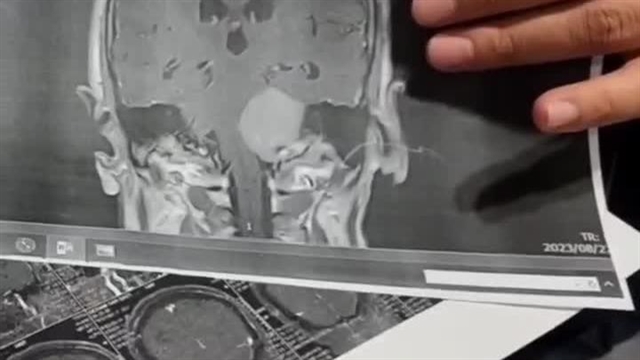

تصویربرداری و ارزیابیهای تکمیلی

- سیتی اسکن (CT Scan): در تشخیص اولیه آسیبهای مغزی ناشی از تومور مؤثر است، اما محدودیتهایی دارد. برخی تومورها مانند کیستهای آراکنوئید ممکن است در CT قابل مشاهده نباشند. همچنین افتراق برخی انواع تومور در این روش دشوار است. با این حال، در شرایط اورژانسی، پیش از آماده شدن نتایج MRI و MRS، جراحان میتوانند بر اساس یافتههای CT اقدامات فوری لازم را انجام دهند.

- امآرآی (MRI) مغز و کانال شنوایی داخلی: تصویربرداری دقیق از ساختارهای نرم ناحیه سی پی انگل و تشخیص نوع و موقعیت تومور.